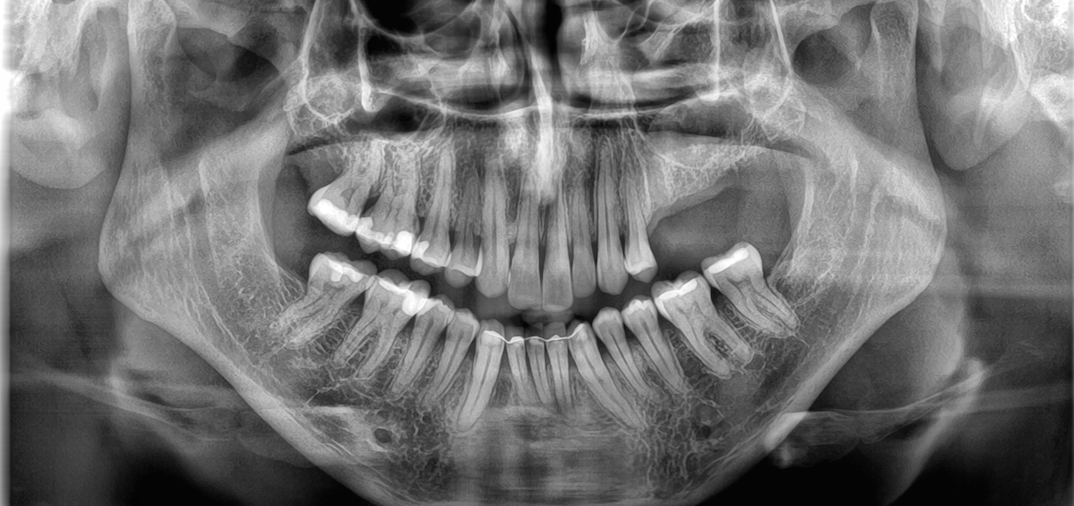

ich habe links im Oberkiefer eine Kieferzyste, die nach der Zahnextraktion der Zähne 25, 26 und 27 entdeckt wurde. Es wurden zuvor bereits eine Wurzelbehandlung und eine Wurzelspitzenresektion durchgeführt, da ich eine Zahnbrücke hatte, die leider aufgegeben werden musste.

Seit einiger Zeit habe ich ein leichtes Kribbeln an der linken Wange und am linken Auge. Der Zahnarzt und der MKG-Chirurg meinen, die Zyste sei harmlos und ein mit Flüssigkeit gefüllter Hohlraum. Allerdings konnte mir bisher niemand genau sagen, um welche Art von Kieferzyste es sich handelt.

wenn es eine zyste wäre, dann würde es wachsen. wenn es zusammen mit den zähnen z.b. im zuge einer tiefen karies, oder einer wwurzelbehandlung aufgetreten ist, dann wäre es eine radikuläre zyste und gehört entfernt.

ich glaube aber, es handelt sich nicht um eine zyste, sondern um einen polypen, der bleibt unverändert groß und man muss nichts machen. ist eine art reaktion der nasennebenhöhlenschleimhaut auf die vorher vorhandenen und entzündeten zähne. was bedeutet entzündet? durch eine große füllung, eine tiefe karies, oder einer schlechten wurzelbehandlung kam es zu infektionen an den wurzelspitzen der zähne. diese entzündungen liegen in unmittelbarer nähe zur kieferhöhle – die schleimhaut reagiert (wie eine hornhaut). wenn die ursache der reizung weg ist, kann die “hornhaut” bleiben.